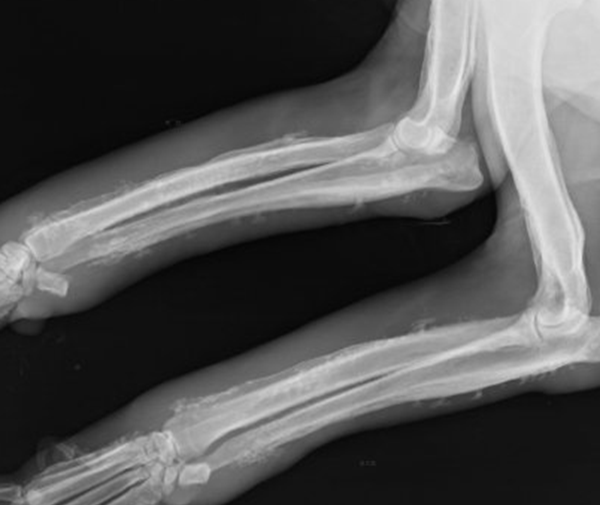

3. 手脚因骨膜增厚呈圆柱状,踝、膝闭节肿胀积液。

查瞅:厚皮性骨膜病的X线查瞅瞅来胫骨、腓骨、桡骨、尺骨等部位有增素性骨膜炎、充溢性骨膜增厚。

诊疗:依据皮肤及骨骼X线查瞅睹增素性骨膜炎、充溢性骨膜增厚的典范临床转变可作出诊疗。